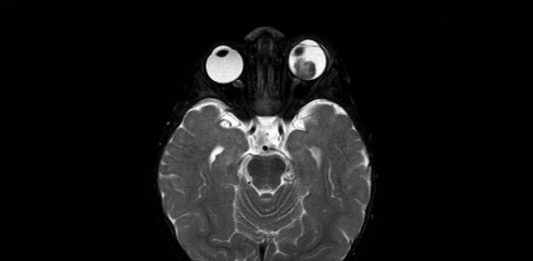

Oncologia oculare pediatrica: approccio clinico, ecografico e diagnosi differenziale in un caso di neoformazione orbitaria